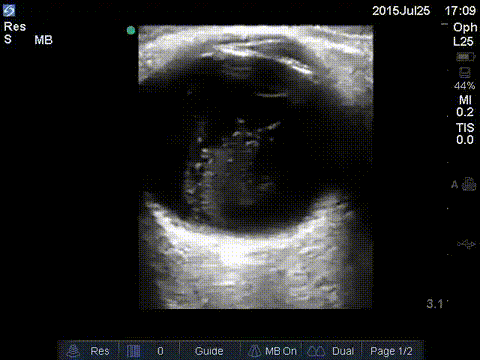

Vitreous hemorrhage vs. Asteroid Hyalosis

Asteroid hyalosis is a degenerative condition of the vitreous with a prevalence of 1.2% in adults. It is found to be more frequent with aging, with 0.2% prevalence in 43- to 54-year-old and 2.9% in 75- to 86-year-old patients. It has been reported to mimic vitreous hemorrhage with the similar washing machine sing seen on ultrasound. On ultrasound there may be echogenic fluid with potential multiple echogenic foci.